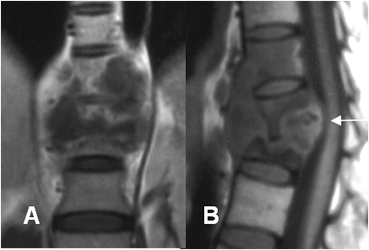

Fig 52 A. Osteomielitis TBC.

A: RM coronal en T1 y B: RM sagital en T1 con contraste. Infección tuberculosa, con compromiso de 3 cuerpos vertebrales. Hay masa de tejidos blandos, con comprime el saco dural.